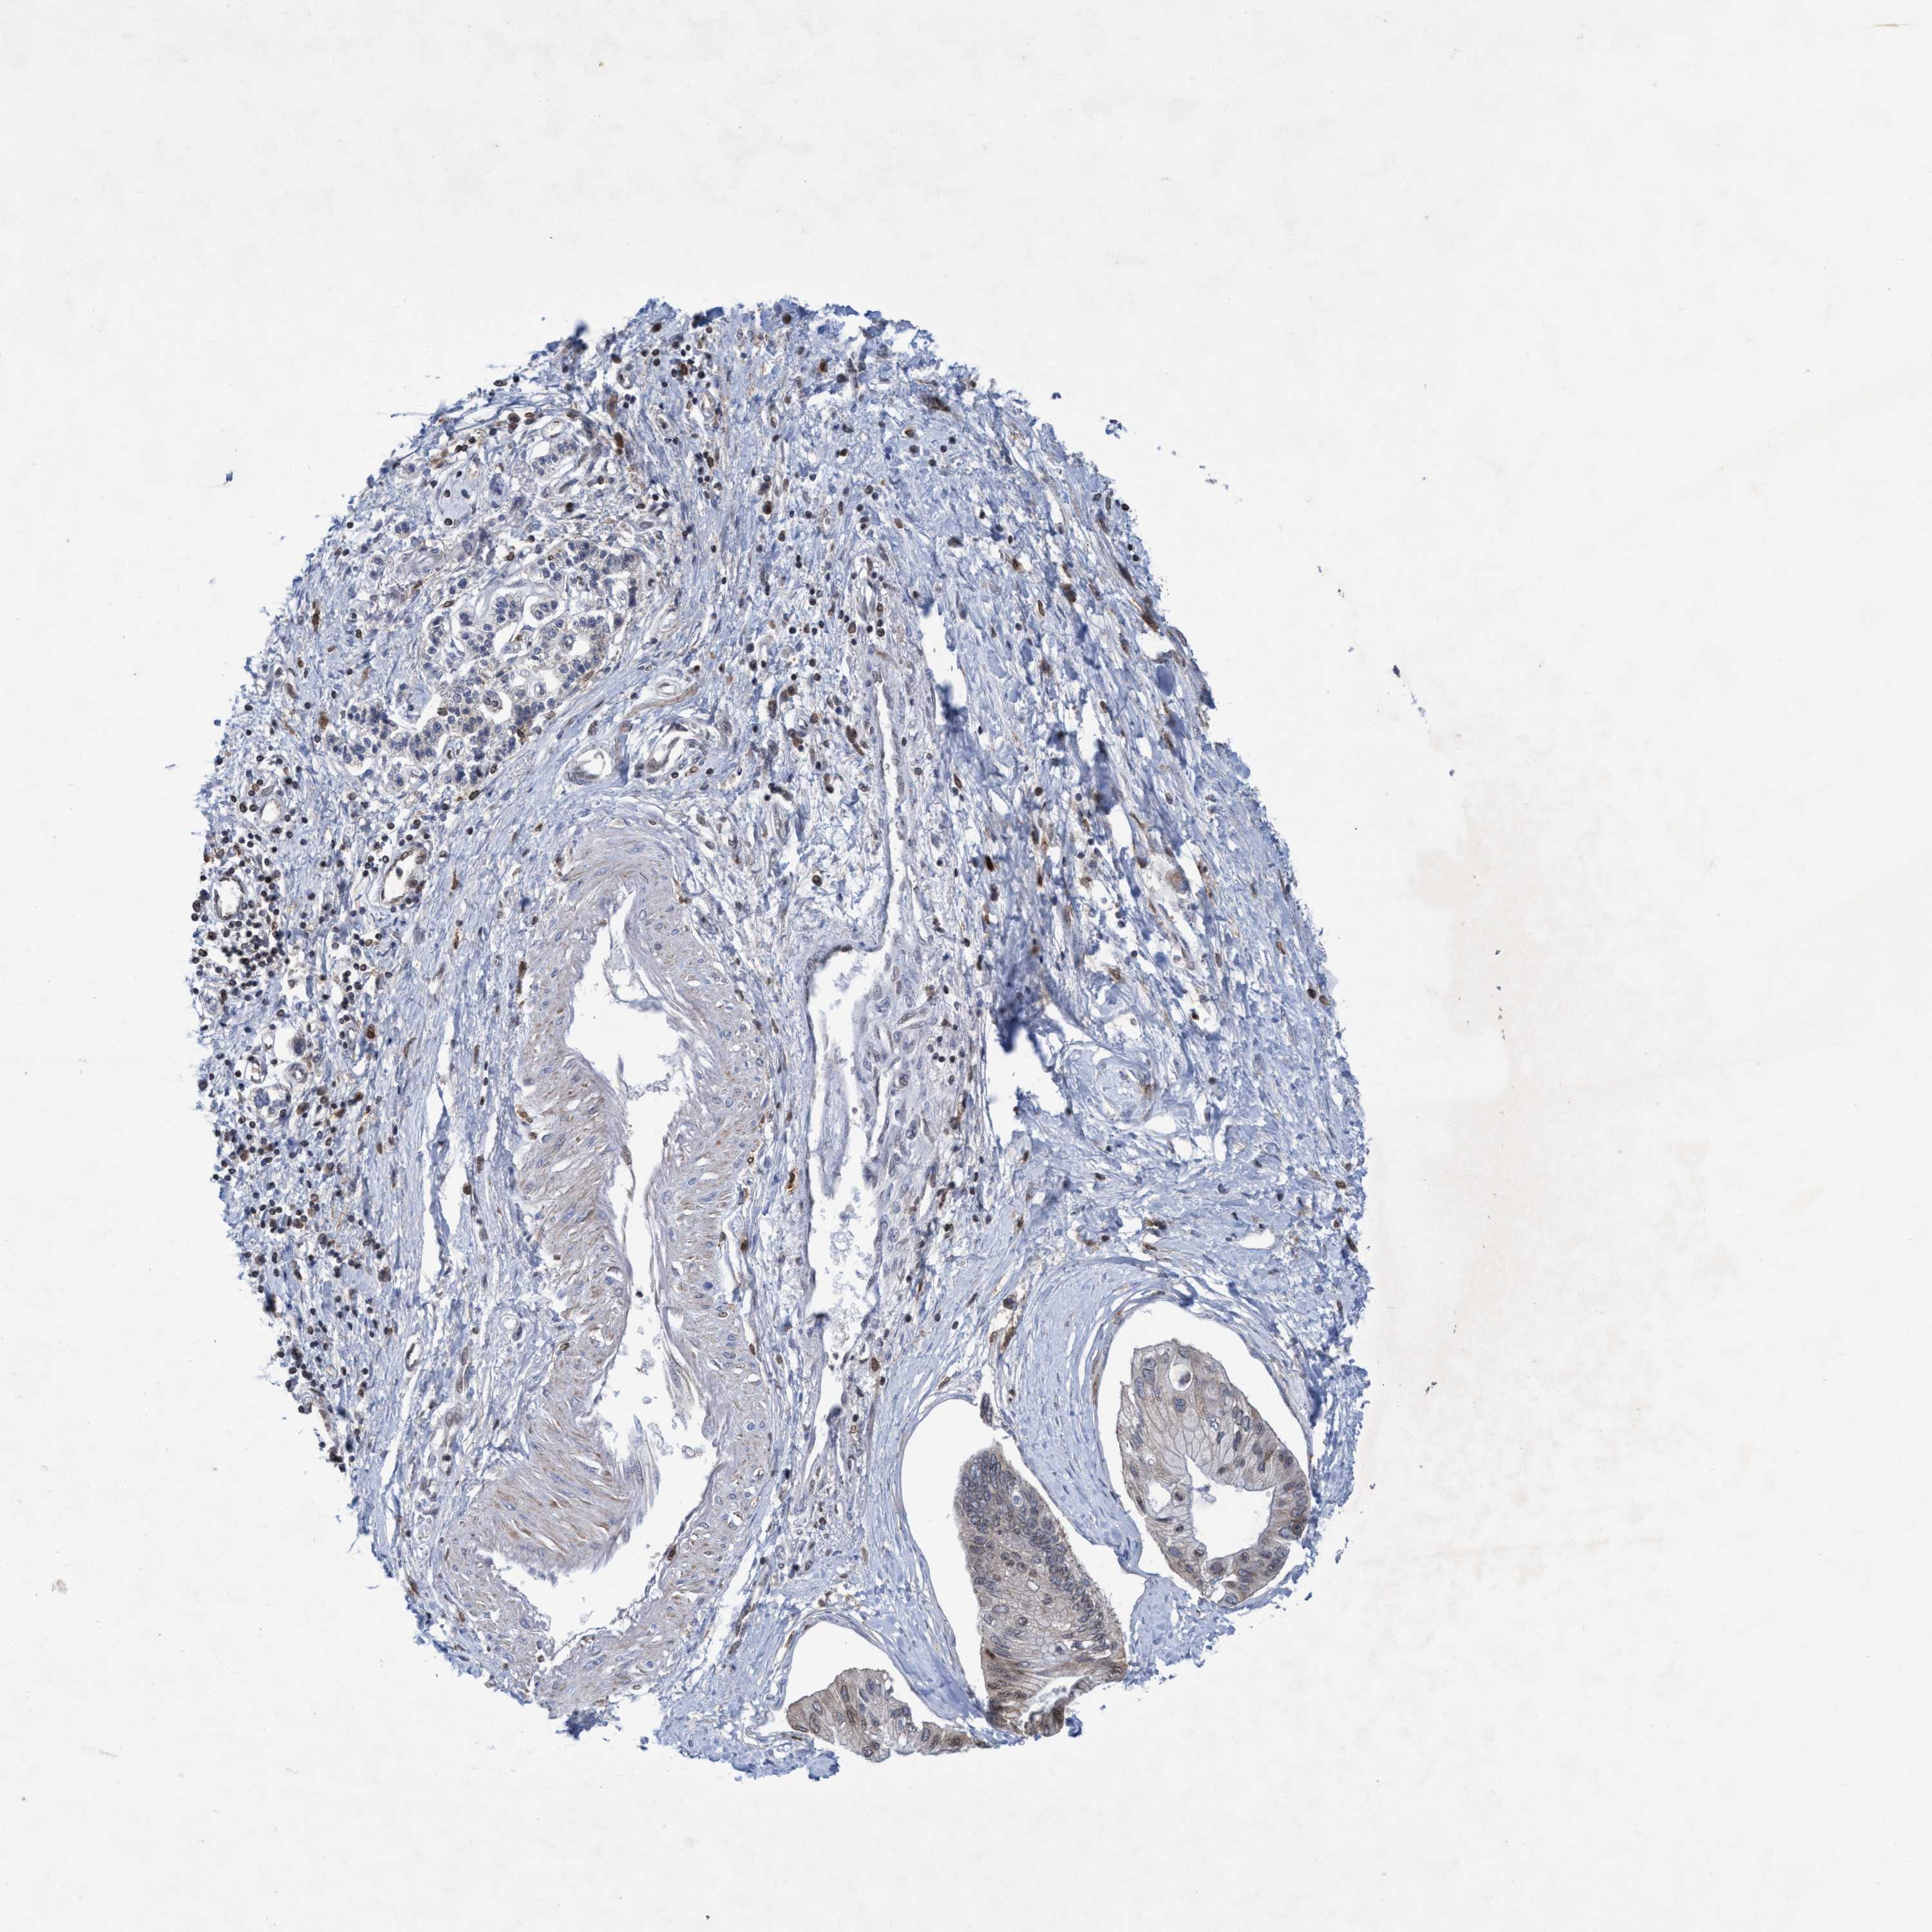

PANCREATIC CANCER - Protein expressioni

A mouse-over function shows sample information and annotation data. Click on an image to view it in a full screen mode. Samples can be filtered based on level of antibody staining by selecting one or several of the following categories: high, medium, low and not detected. The assay and annotation is described here.

Note that samples used for immunohistochemistry by the Human Protein Atlas do not correspond to samples in the TCGA dataset.

Antibody stainingi

Antibody staining in the annotated cell types in the current human tissue is reported as not detected, low, medium, or high, based on conventional immunohistochemistry profiling in selected tissues. This score is based on the combination of the staining intensity and fraction of stained cells.

Each image is clickable and will lead to virtual microscopy that enables deeper exploration of all samples and also displays staining intensity scores, fraction scores and subcellular localization as well as patient and tissue information for each sample.

Antibody HPA021451

Antibody CAB017490

Staining

High

Medium

Low

Not detected

Intensity

Strong

Moderate

Weak

Negative

Quantity

>75%

75%-25%

<25%

None

Location

Nuclear

Cytoplasmic/membranous

Cytoplasmic/membranous,nuclear

Adenocarcinoma, NOS